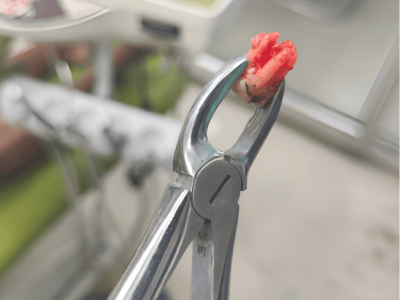

provides expert treatment for gum diseases, receding gums, and dental implant procedures using the

the best possible care for every patient. Whether you need routine checkups or complex periodontal

From routine checkups to complex gum treatments, dental implants, laser dentistry, root canal treatments (RCT), and smile